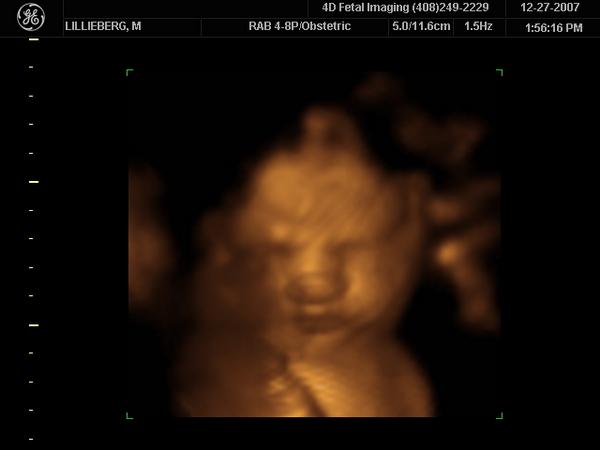

Enjoying Every Moment With My Daughter..

I've already met her.My little Ava.